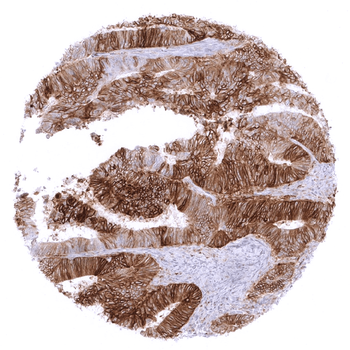

Colon Colorectal adenocarcinoma with moderate to strong membranous PD L1 staining in the vast majority of its tumor cells.